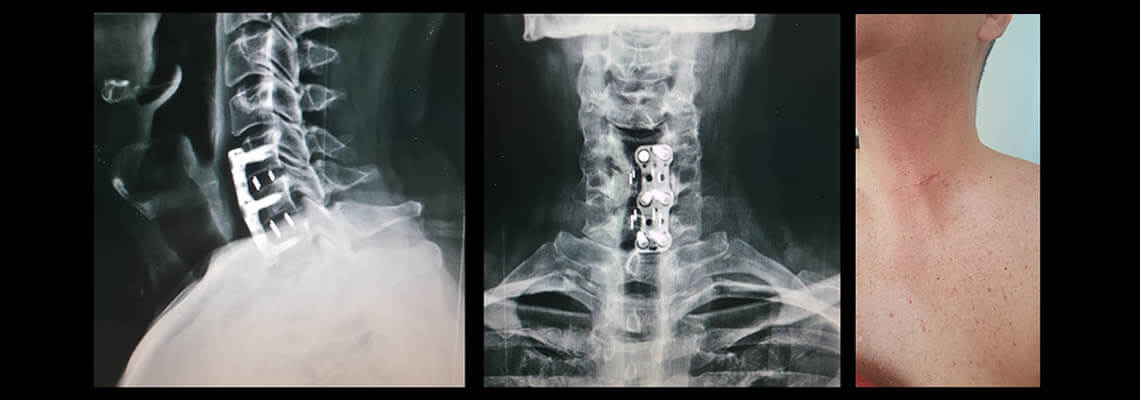

Dolor de Cuello